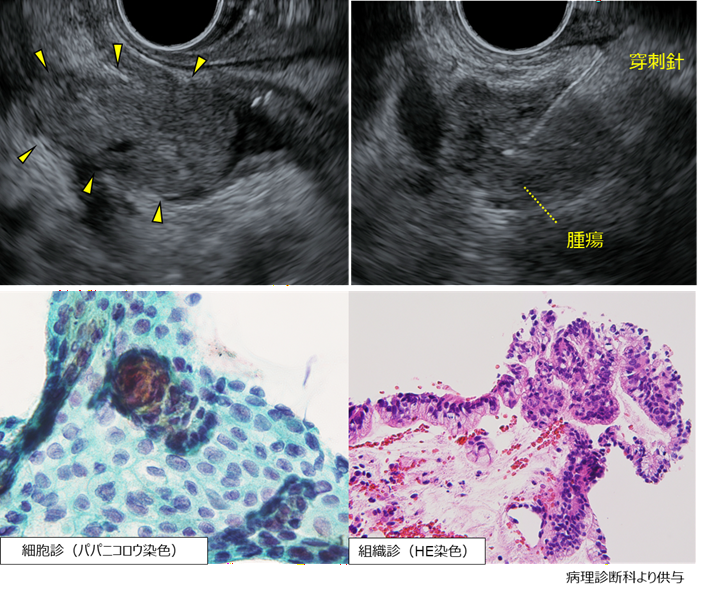

EUS-FNAで採取された検体

細胞診(左)および組織診(右)ともに腺癌の診断でした。

EUS-FNAで採取された組織は、確実な診断のために十分な組織が採取されていました。

以上から、stage Iの膵癌の診断となり、術前化学療法を実施の上で膵頭十二指腸切除を施行し、完全に切除ができました。

外科切除された検体では、大きさ7mmの浸潤性膵管癌でリンパ節転移はなく、stage I (T1bN0M0)でした。

現在、再発なく経過しています。